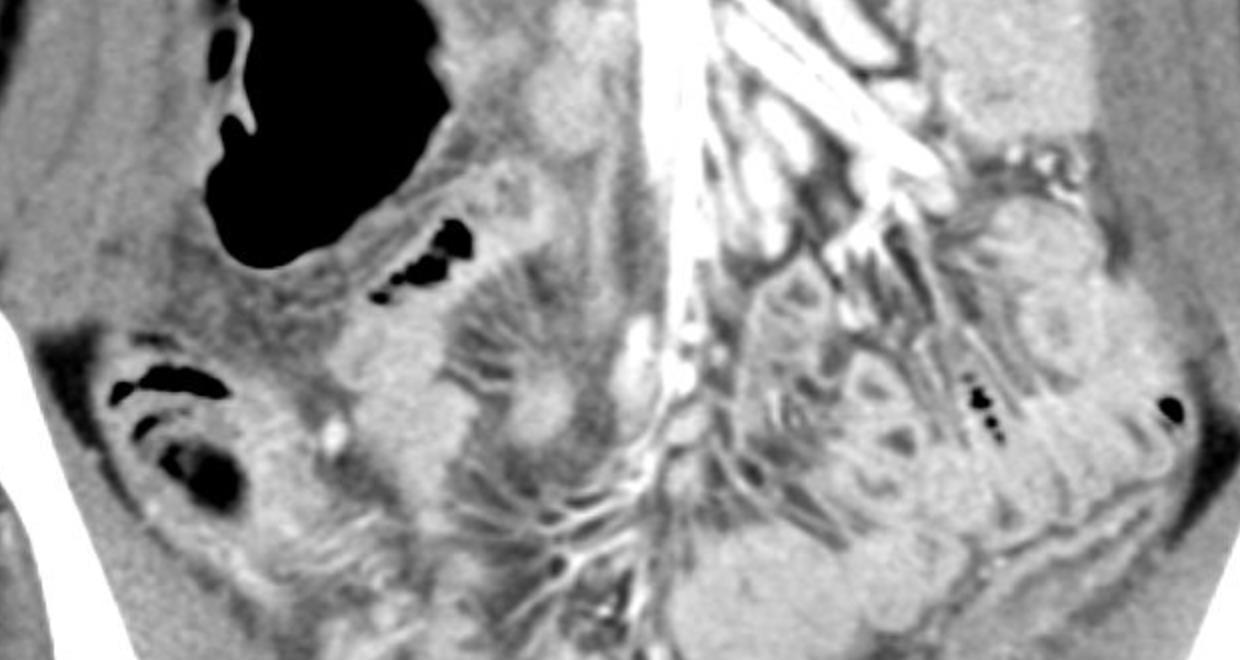

Pediatric COVID-19: MIS-C

Abdominal abnormalities

Hollow viscera abnormalities

Gallbladder wall thickening

Bowel wall thickening

Bowel dilation

Gastric distention

Urinary bladder thickening

Peritoneal abnormalities

Small ascites

Mesenteric abnormalities

Mesenteric lymphadenopathy

• Gastrointestinal (GI) symptoms (abdominal pain, diarrhoea and vomiting) are prevalent in MIS-C

• Abdominal pain in 62%

• Up to 90% any GI symptom

• Anumber of studies have described abdominal imaging findings including ascites, bowel wall thickening and mesenteric lymphadenopathy